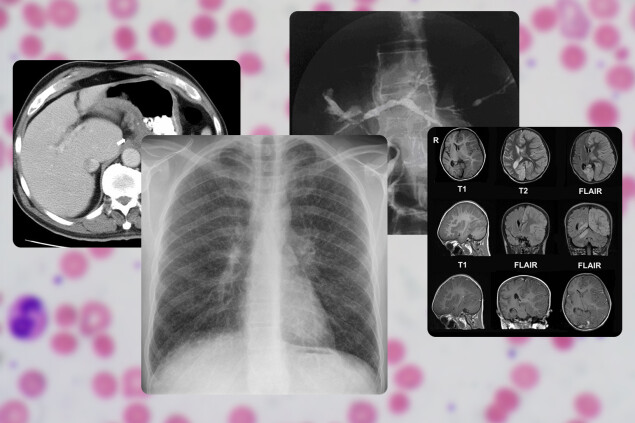

Чтобы установить конкретное заболевание, необходимо провести ряд анализов и исследований по показаниям врача. Например, антинуклеарные антитела (ANA) в крови указывают на аутоиммунную активность в организме, а УЗИ, КТ, МРТ и биопсия помогают обнаружить повреждения органов и тканей.